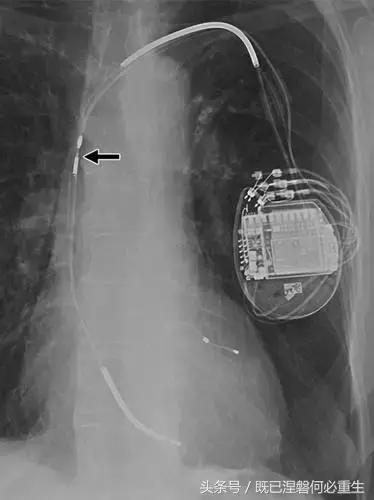

图5C,70岁女性心室穿孔。 正位胸片显示,圣犹达医疗双室起搏器的RV导联(箭头)超出心室轮廓。 心肌穿孔很少会导致放血或压塞。 患者没有受到并发症或随后的铅改变的不良影响(修订电极显示)。 心室穿孔可能导致对膜片的不适当刺激。